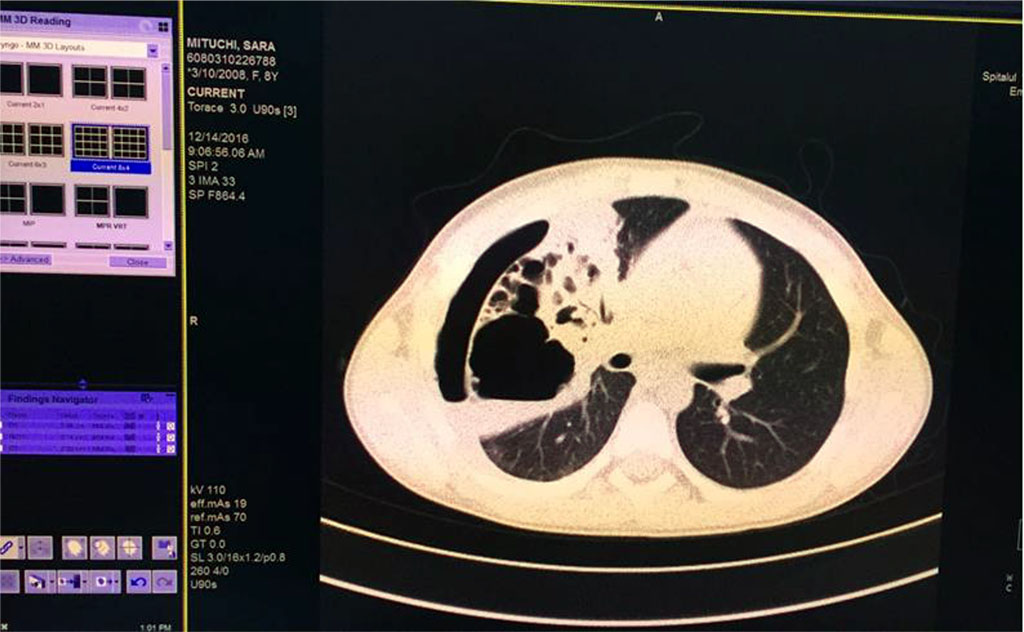

We’ve started the treatment with Ceftriaxone and Gentamicin with unfavorable evolution, increasing chest pain and dyspnea. Our second option was an association between Piperacillin/ Tazobactam without improvement of general state and maintaining of abnormal blood tests. Therefore, thoracic computed tomography was performed (Fig 5,6,7). It revealed the presence of right Pyo-pneumothorax. In that case a pleural drainage was performed in association with large spectrum antibiotic therapy (Meropenem, Linezolid, Metronidazole).

Fig. 7. Pulmonary consolidation, inhomogenous, with multiple aeric cysts with sizes from 11mm to 42.3mm